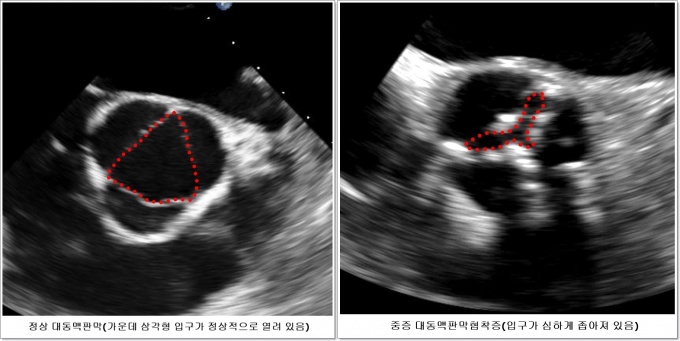

´ëµ¿¸ÆÆÇ¸·ÇùÂøÁõÀº ¼±Áø±¹¿¡¼­ ÃÖ±Ù °¡Àå ¸¹ÀÌ ¹ß»ýÇÏ´Â ½ÉÀåÆÇ¸· ÁúȯÀ¸·Î Àα¸ °í·ÉÈ­¿¡ µû¶ó À¯º´·üÀÌ Áõ°¡ÇÏ´Â ´ëÇ¥ÀûÀÎ ¸¸¼ºÁúȯÀÌ´Ù. ´ëµ¿¸ÆÆÇ¸· ±³Ã¼¼úÀº °¡Àå È¿°úÀûÀΠǥÁØÄ¡·á·Î ¾Ë·ÁÁ® ÀÖ´Ù.

ÁßÁõ ´ëµ¿¸ÆÆÇ¸·ÇùÂøÁõ ȯÀÚ Áß 3ºÐÀÇ 1Àº ¹«Áõ»óÀ¸·Î ½ÉÀåÃÊÀ½ÆÄ µîÀ» ÅëÇØ ¿ì¿¬È÷ ¹ß°ßµÈ´Ù. Áö±Ý±îÁö´Â Áø´ÜµÇ´õ¶óµµ Æ¯º°ÇÑ Ä¡·á ¾øÀÌ ÁÖÀÇ ±í°Ô °üÂûÇÏ´Ù°¡ Áõ»óÀÌ ¹ß»ýÇÏ¸é ´ëµ¿¸ÆÆÇ¸· ±³Ã¼¼ö¼úÀ» ¹Þµµ·Ï ±ÇÀåÇß´Ù.

°­ ±³¼öÆÀÀº 2010³â 7¿ùºÎÅÍ 2015³â 4¿ù±îÁö ÆÇ¸· ÀÔ±¸°¡ 0.75§² ÀÌÇÏ·Î Á¼¾ÆÁ® ÀÖ¾î ÁßÁõÀÌÁö¸¸ Áõ»óÀÌ ¾ø´Â ¹«Áõ»ó ´ëµ¿¸ÆÆÇ¸·ÇùÂøÁõ ȯÀÚ 145¸í Áß º¸Á¸Àû Ä¡·á¸¦ ¹ÞÀº 72¸í°ú Áø´Ü ÈÄ 2°³¿ù ¾È¿¡ Á¶±â ¼ö¼úÀ» ¹ÞÀº 73¸íÀ» ÃßÀû °üÂûÇß´Ù.